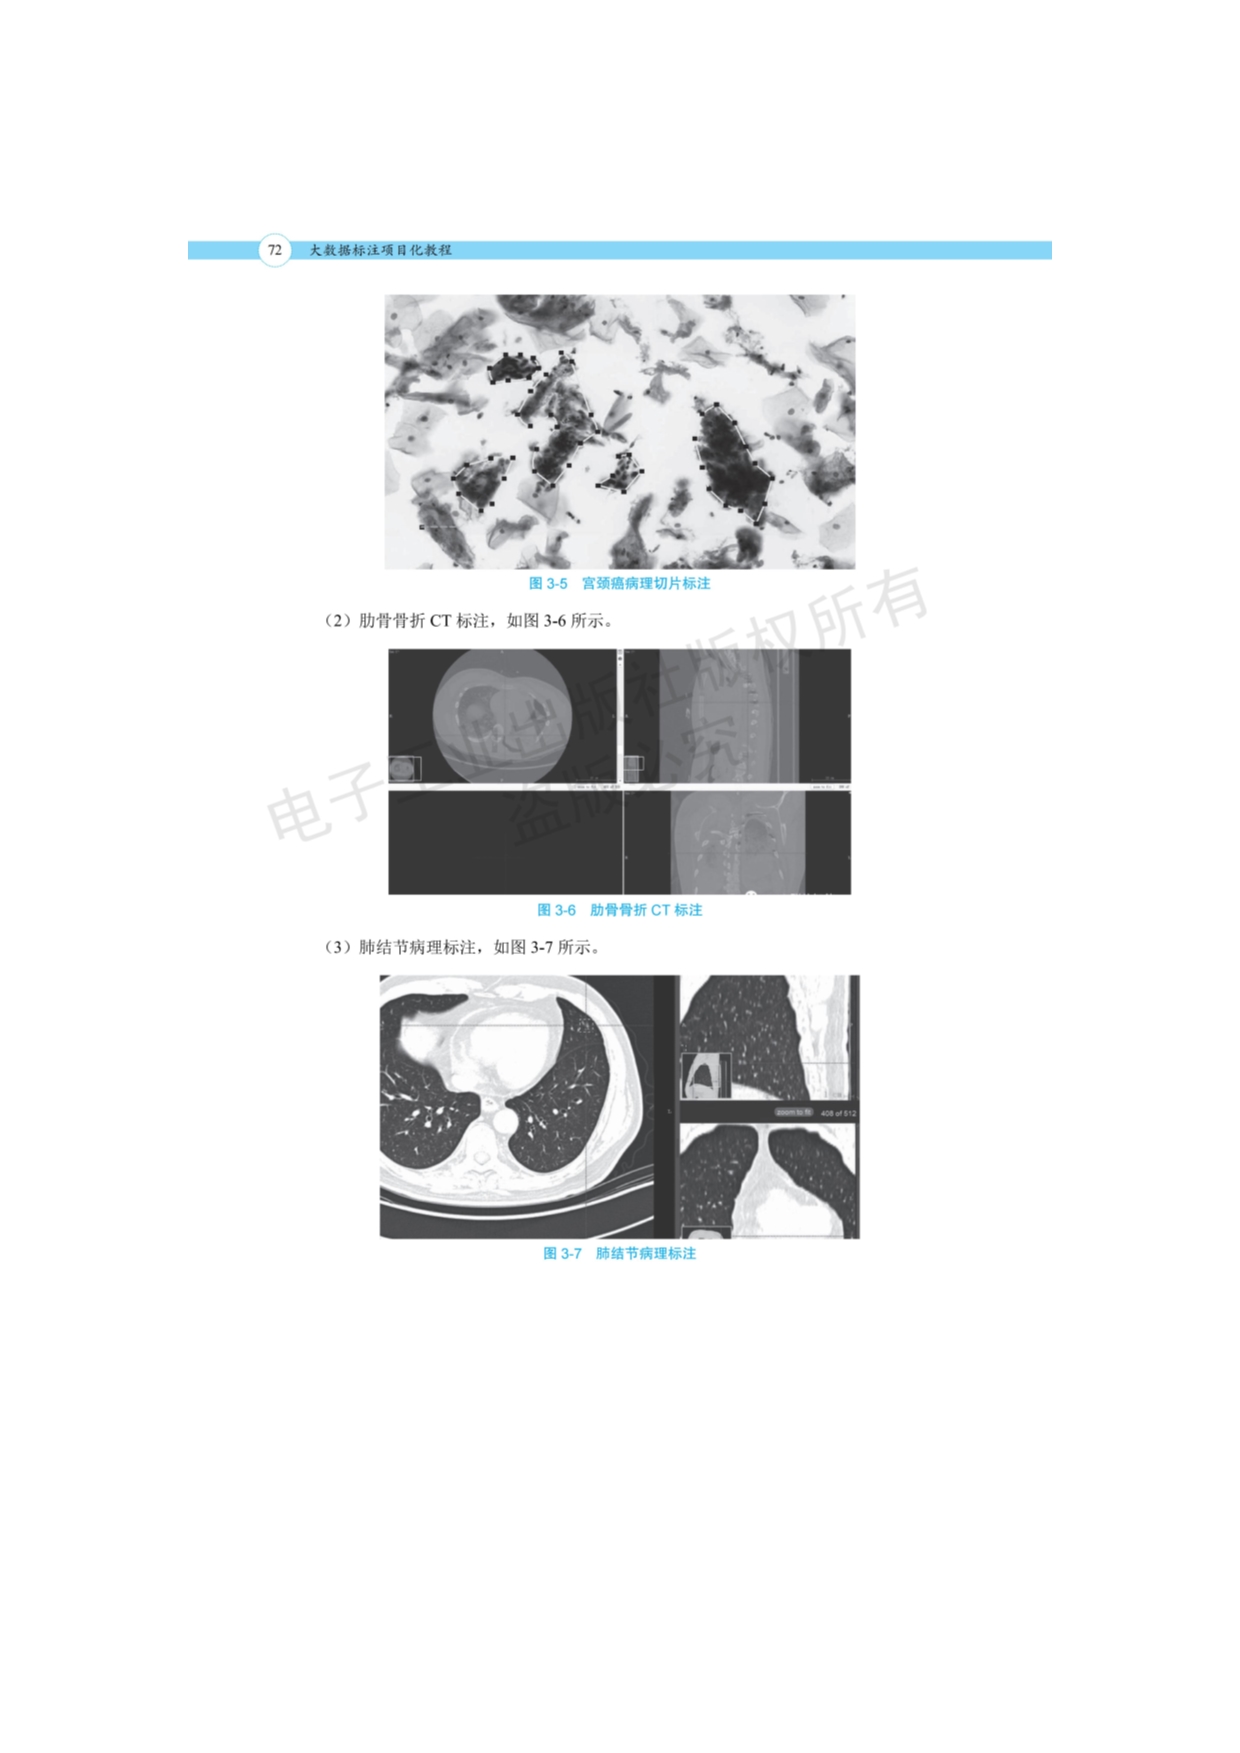

253.《数据标注工程——概念、方法、工具与案例》+聂明+人工智能学院